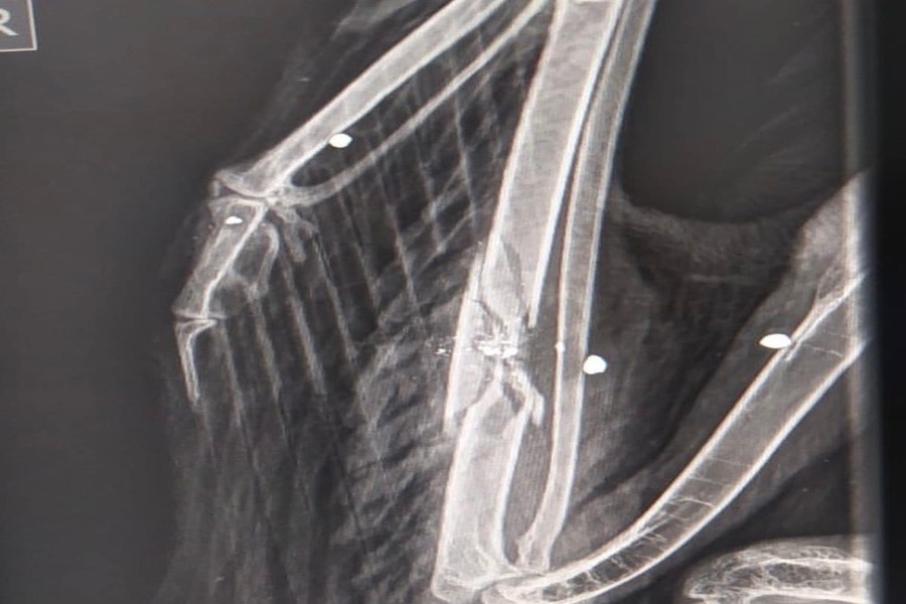

El equipo de rescate de la Corporación llegó hasta Toche, corregimiento de Ibagué, para recibir un Águila Real de Páramo de nombre científico (Geranoetus melanoleucus) la cual fue atacada con 5 perdigones.

El ave presenta fractura de ulna o cúbito del ala derecha y tiene algunos perdigones incrustados en el tejido muscular.